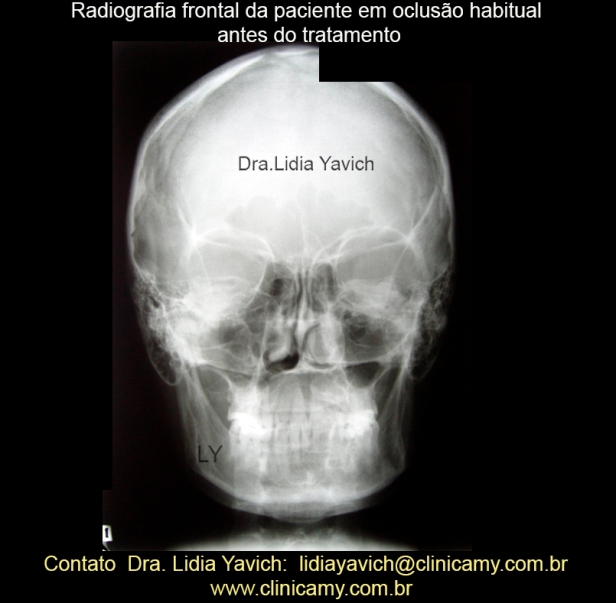

Radiografia frontal da paciente em oclusão habitual antes do tratamento.

Radiografia frontal da paciente em oclusão habitual antes do tratamento.